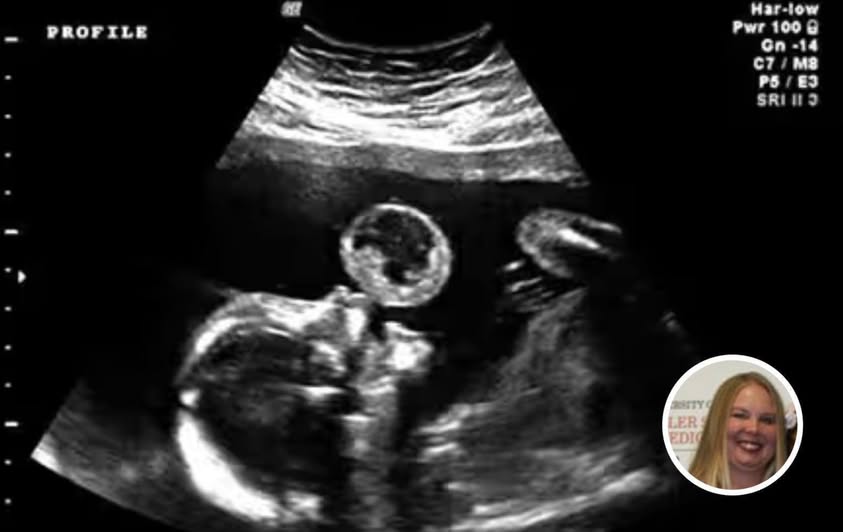

Tammy Gonzalez arrived at her scheduled ultrasound appointment expecting a familiar and joyful milestone. Like many parents-to-be, she looked forward to seeing her baby on screen. However, the mood shifted within moments when medical staff noticed an unusual formation near the baby’s mouth.

Further examination revealed that the growth was not a simple imaging irregularity, but a rare medical condition known as a teratoma. While uncommon, its location posed serious risks, particularly the possibility of obstructing the baby’s airway after birth.

Her decision led her to a specialized medical team capable of performing an advanced fetal intervention. The procedure, described as minimally invasive, involved navigating delicate instruments inside the womb to address the immediate threat posed by the tumor.

The goal was not full removal, but reducing the risk—specifically preventing the growth from interfering with the baby’s development and ability to breathe after birth.